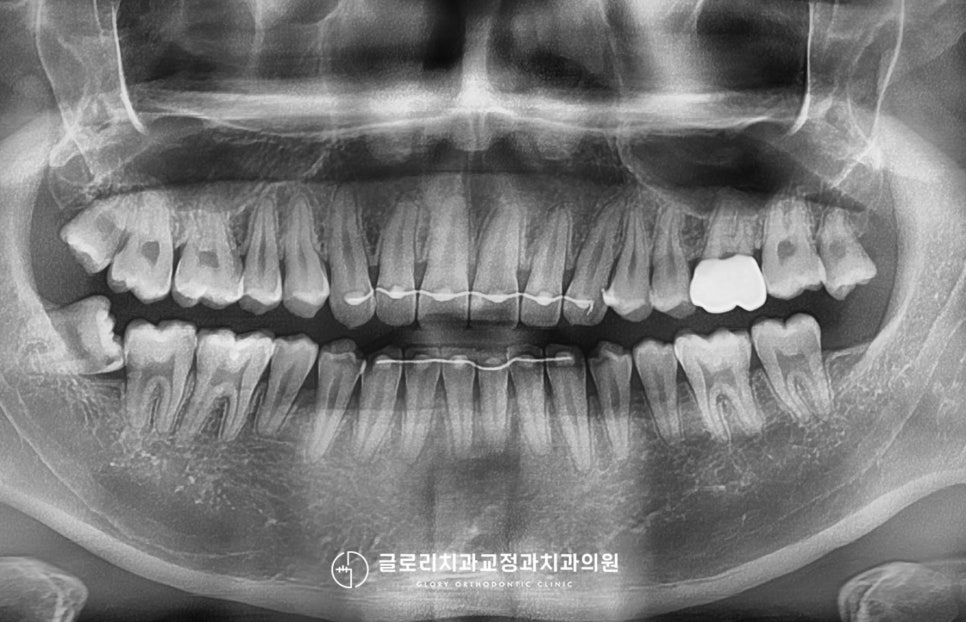

망우동 치과 에서 2달에 걸친 과정이

끝이 났는데요.

환자께서 개선을 원하셨던 부분이

MTA를 통해 잘 치료가 되었습니다.

앞니 급속 교정을 통해 신속하게 시행되어

시간도 단축되고 불편감도 적은 편이라

생활하는 데에도 큰 문제가 없어

좋았다고 말씀해 주셨습니다.

치료 기간: 23.05.25~24.08.22